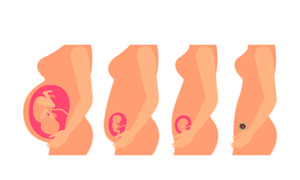

现在很多的女性朋友都懂得如何科学的孕育,在准备怀孕之前会有备孕的过程。备孕要让子宫变得干净,像是迎接新的客人一样,将房子打扫干净,等待客人居住。清洁子宫有很多方法,那么怎样让子宫干净好备孕呢?

女性在怀孕之后会有很多的产前项目需要进行检查,以确定胎儿宝宝和女性的身体是否处于正常情况。而这些较多的产前检查项目,有时候也会让孕妈妈感觉到奔波的很疲惫。那么在孕期产检项目哪些没必要做呢?

在孕期准妈妈所要做的孕期检查确实有很多种,比如最常见的有血常规检查,尿常规检查,B超检查,彩超检查,胎儿的心率监测,四维彩超畸形检查以及早唐筛查,中唐筛查等等,这些检查项目涵盖了整个孕期的孕早期,孕中期和孕晚期以及临产前的各个阶段的检查。

这些检查都是针对胎儿发育的各个时期,来检测胎儿是否正常。因为一旦胎儿或准妈妈的身体出现异常情况,可以通过产前检查来第一时间发现问题,这就可以将一些怀孕期间的某些风险降至最低,并且如有异常也可以第一时间采取有效的处理办法和调理治疗措施。

因此在个人建议上,准妈妈对于产检所包含的各个阶段的孕期检查,还是要遵循妇产科检查程序来进行,并且在孕期也要遵循专业医师的意见和建议,进行孕期的保健和调理,这样才能让胎儿宝宝健康的发育。